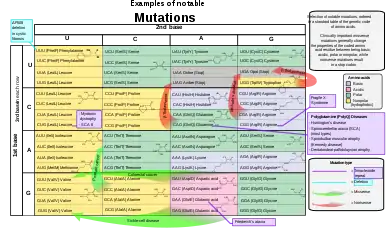

Classification of types

By effect on structure

The sequence of a gene can be altered in a number of ways.[44] Gene mutations have varying effects on health depending on where they occur and whether they alter the function of essential proteins. Mutations in the structure of genes can be classified into several types.

Small-scale mutations

Small-scale mutations affect a gene in one or a few nucleotides. (If only a single nucleotide is affected, they are called point mutations.) Small-scale mutations include:

- Insertions add one or more extra nucleotides into the DNA. They are usually caused by transposable elements, or errors during replication of repeating elements. Insertions in the coding region of a gene may alter splicing of the mRNA (splice site mutation), or cause a shift in the reading frame (frameshift), both of which can significantly alter the gene product. Insertions can be reversed by excision of the transposable element.

- Deletions remove one or more nucleotides from the DNA. Like insertions, these mutations can alter the reading frame of the gene. In general, they are irreversible: Though exactly the same sequence might, in theory, be restored by an insertion, transposable elements able to revert a very short deletion (say 1–2 bases) in any location either are highly unlikely to exist or do not exist at all.

- Substitution mutations, often caused by chemicals or malfunction of DNA replication, exchange a single nucleotide for another.[45] These changes are classified as transitions or transversions.[46] Most common is the transition that exchanges a purine for a purine (A ↔ G) or a pyrimidine for a pyrimidine, (C ↔ T). A transition can be caused by nitrous acid, base mispairing, or mutagenic base analogs such as BrdU. Less common is a transversion, which exchanges a purine for a pyrimidine or a pyrimidine for a purine (C/T ↔ A/G). An example of a transversion is the conversion of adenine (A) into a cytosine (C). Point mutations are modifications of single base pairs of DNA or other small base pairs within a gene. A point mutation can be reversed by another point mutation, in which the nucleotide is changed back to its original state (true reversion) or by second-site reversion (a complementary mutation elsewhere that results in regained gene functionality). As discussed below, point mutations that occur within the protein coding region of a gene may be classified as synonymous or nonsynonymous substitutions, the latter of which in turn can be divided into missense or nonsense mutations.

By impact on protein sequence

The effect of a mutation on protein sequence depends in part on where in the genome it occurs, especially whether it is in a coding or non-coding region. Mutations in the non-coding regulatory sequences of a gene, such as promoters, enhancers, and silencers, can alter levels of gene expression, but are less likely to alter the protein sequence. Mutations within introns and in regions with no known biological function (e.g. pseudogenes, retrotransposons) are generally neutral, having no effect on phenotype – though intron mutations could alter the protein product if they affect mRNA splicing.

Mutations that occur in coding regions of the genome are more likely to alter the protein product, and can be categorized by their effect on amino acid sequence:

- A frameshift mutation is caused by insertion or deletion of a number of nucleotides that is not evenly divisible by three from a DNA sequence. Due to the triplet nature of gene expression by codons, the insertion or deletion can disrupt the reading frame, or the grouping of the codons, resulting in a completely different translation from the original.[47] The earlier in the sequence the deletion or insertion occurs, the more altered the protein produced is. (For example, the code CCU GAC UAC CUA codes for the amino acids proline, aspartic acid, tyrosine, and leucine. If the U in CCU was deleted, the resulting sequence would be CCG ACU ACC UAx, which would instead code for proline, threonine, threonine, and part of another amino acid or perhaps a stop codon (where the x stands for the following nucleotide).) By contrast, any insertion or deletion that is evenly divisible by three is termed an in-frame mutation.

- A point substitution mutation results in a change in a single nucleotide and can be either synonymous or nonsynonymous.

- A synonymous substitution replaces a codon with another codon that codes for the same amino acid, so that the produced amino acid sequence is not modified. Synonymous mutations occur due to the degenerate nature of the genetic code. If this mutation does not result in any phenotypic effects, then it is called silent, but not all synonymous substitutions are silent. (There can also be silent mutations in nucleotides outside of the coding regions, such as the introns, because the exact nucleotide sequence is not as crucial as it is in the coding regions, but these are not considered synonymous substitutions.)

- A nonsynonymous substitution replaces a codon with another codon that codes for a different amino acid, so that the produced amino acid sequence is modified. Nonsynonymous substitutions can be classified as nonsense or missense mutations:

- A missense mutation changes a nucleotide to cause substitution of a different amino acid. This in turn can render the resulting protein nonfunctional. Such mutations are responsible for diseases such as Epidermolysis bullosa, sickle-cell disease, and SOD1-mediated ALS.[48] On the other hand, if a missense mutation occurs in an amino acid codon that results in the use of a different, but chemically similar, amino acid, then sometimes little or no change is rendered in the protein. For example, a change from AAA to AGA will encode arginine, a chemically similar molecule to the intended lysine. In this latter case the mutation will have little or no effect on phenotype and therefore be neutral.

- A nonsense mutation is a point mutation in a sequence of DNA that results in a premature stop codon, or a nonsense codon in the transcribed mRNA, and possibly a truncated, and often nonfunctional protein product. This sort of mutation has been linked to different diseases, such as congenital adrenal hyperplasia. (See Stop codon.)